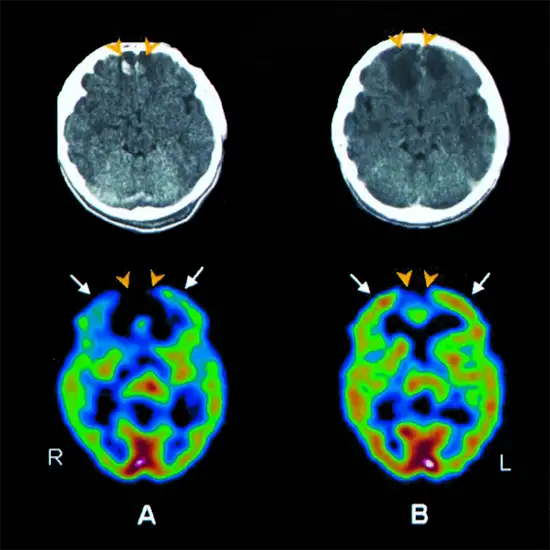

A brain scan called a SPECT cerebral perfusion scan measures the amount of blood absorbed in specific regions of your brain. This can reveal details about the way your brain works. The many forms of brain perfusion scans are as follows.

Some diagnostic procedures involve radiotracers, which are radioactive compounds that release minute particles, such as single photon emission computed tomography (SPECT) or positron emission tomography (PET) scans.

In addition to other types of common imaging tests, including a computed tomography (CT) scan, healthcare professionals frequently superimpose images of cerebral perfusion. As a result, they can compare the data from the two methodologies on a single image.